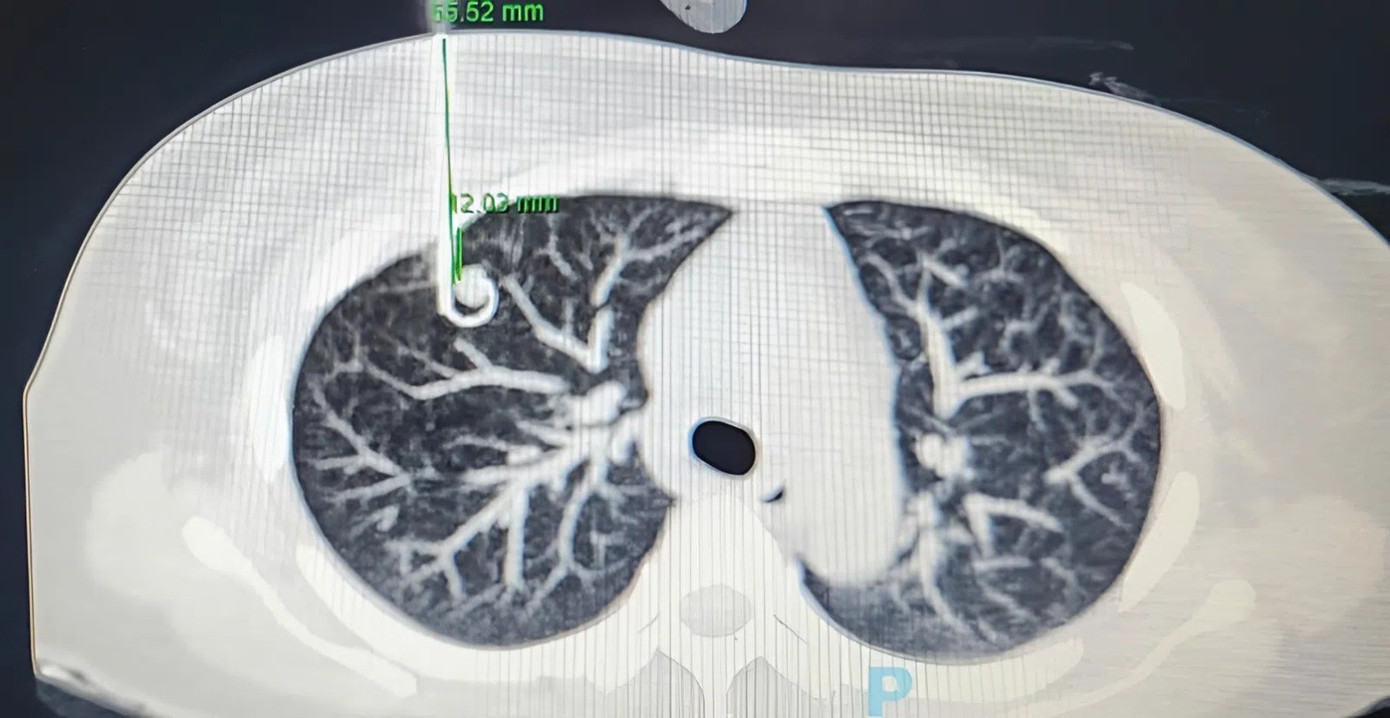

Đó là trường hợp bệnh nhân N.T.K.C. (50 tuổi, ngụ tại TP.HCM) vừa được tiếp nhận, điều trị tại Bệnh viện Chợ Rẫy. Ngày 27/10, TS.BS Nguyễn Hoàng Bình, Trưởng khoa Ngoại Lồng ngực của bệnh viện cho biết, bà C. là một trong những trường hợp may mắn được phát hiện sớm ung thư phổi. Trong lần kiểm tra sức khỏe định kỳ tại Bệnh viện Chợ Rẫy, trên hình ảnh CT các bác sĩ ghi nhận bệnh nhân có nốt mờ khoảng 11mm ở thùy trên phổi bên phải.

Trên hình ảnh kiểm tra, các bác sĩ phát hiện nốt mờ nhỏ bất thường trong phổi người bệnh

Theo bệnh sử, trước đó, bà C. hoàn toàn không có triệu chứng bất thường. Tuy nhiên, kết quả PET/CT các bác sĩ ghi nhận các dấu hiệu nghi ngờ ung thư phổi giai đoạn sớm, chưa có hạch trung thất, chưa di căn xa.

Sau hội chẩn các bác sĩ đã quyết định thực hiện cuộc phẫu thuật cho người bệnh. Ê kíp bác sĩ đã tiến hành định vị vùng tổn thương ở người bệnh bằng kim trước mổ. Bệnh nhân được phẫu thuật nội soi robot cắt thùy phổi phải và nạo hạch. Cuộc phẫu thuật diễn ra thuận lợi, vùng tổn thương phổi được loại bỏ hoàn toàn.